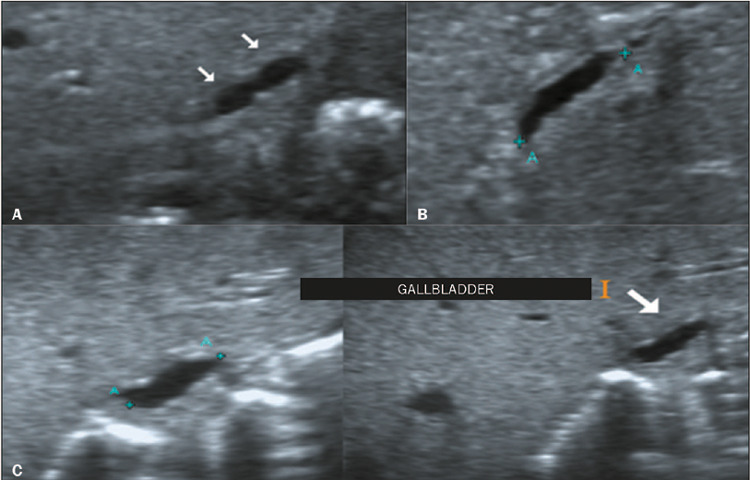

Materials and methods: This was a retrospective study of the ultrasound images of 44 patients with neonatal cholestasis. We excluded 18 patients in whom a final diagnosis of BA was not confirmed or who were lost to clinical follow-up. The main ultrasound findings evaluated were gallbladder length and morphology; triangular cord thickness; hepatic artery enlargement; hepatic subcapsular flow; cysts in the porta hepatis; presence of a distinct triangular cord with linear, tubular, or round hypoechoic portions; and polysplenia syndrome.

Results: Abnormal gallbladder morphology and triangular cord thickening were the main ultrasound findings in the patients with BA. Gallbladder abnormalities were present in all patients. Hepatic artery enlargement was the third most common finding, present in 19 (73%) patients. Six patients (23%) had subcapsular arterial flow and four (15%) had cysts in the porta hepatis. Hypoechoic or cystic portions of the triangular cord were present in three patients (11%), and we found that BA was accompanied by polysplenia syndrome in three patients (11%).